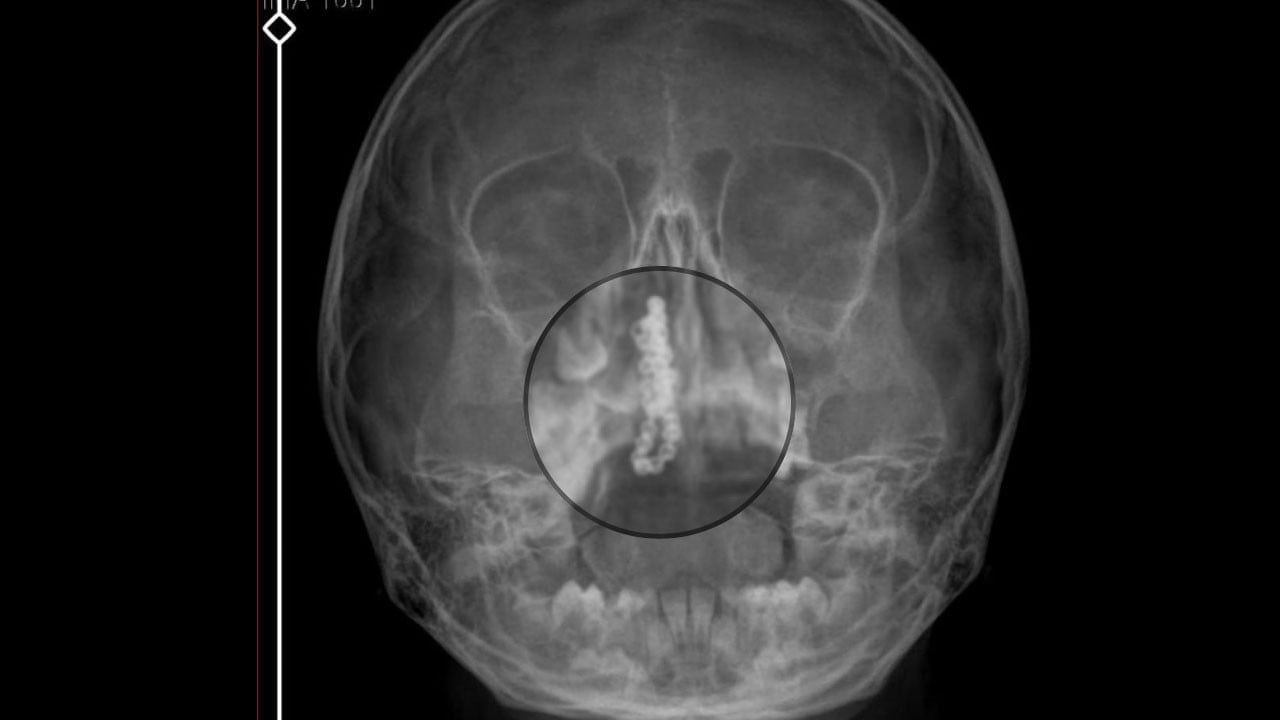

Rize’de 5 yaşındaki Polen Tekin’in burnundan çıkan cisim, duyanları şaşkına çevirdi. Şiddetli burun kanaması ve akıntı şikayetleriyle ailesi tarafından götürüldüğü özel hastanede ilaç verilen Polen Tekin (5), taburcu edildi. Kanamanın sürmesi üzerine bu kez devlet hastanesine götürülen küçük kızın burnunda tespit edilen tırnak makası zinciri ameliyatla çıkarıldı. Baba Gökhan Tekin, suç duyurusunda bulunacaklarını belirterek, "Zincir, 2 yıldır burnunda ve devletimizin hastanesinde iyi bir doktorumuz zinciri ortaya çıkarıyor, kızım ölümden dönüyor" dedi.

Kentte yaşayan Gökhan-Nalan Tekin çifti, yaklaşık 4 ay önce şiddetli burun kanamasının yanı sıra akıntı şikayetleriyle kızları Polen'i, bir özel hastaneye götürdü. Burada röntgeni çekilip, tetkikleri tamamlanan küçük kıza, iddiaya göre enfeksiyon teşhisi konulup, ilaç verildi. Eve dönen aile, kanama ve akıntının geçmemesi üzerine bu kez Rize Devlet Hastanesi'ne giderek Kulak Burun Boğaz Polikliniği'ne başvurdu. Devlet hastanesindeki doktorun incelemesi ve kapsamlı röntgen çekilmesi sonrası Polen'in burnunda metal cisim olduğu fark edildi. 2 yıldır burunda kaldığı değerlendirilip, küçük top şeklinde tırnak makası zinciri olduğu belirlenen cisim, başarılı ameliyatla çıkarıldı. Bir süre tedavisi sürdürülen Polen, sağlığına kavuşunca taburcu edildi. Özel hastane yetkilileri, konuyla ilgili açıklama yapmazken; aile suç duyurusunda bulunacaklarını söyledi.